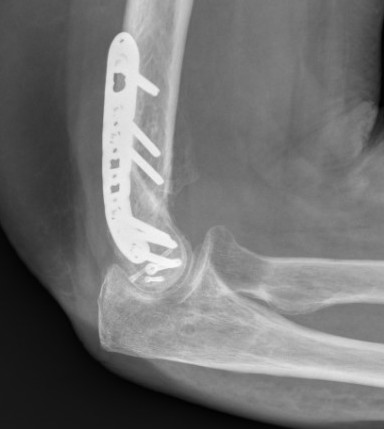

Lateral approach and ORIF

Arm on side table with tourniquet

- lateral approach centered on lateral epicondyle

- split extensor muscle

- open capsule and identify capitellum fracture

- reduce fracture

Usually AP headless compression screws (violates articular surface)

- +/- PA screws (risk AVN)

- +/- excise isolated cartilage lesions

- +/- postero-lateral plate